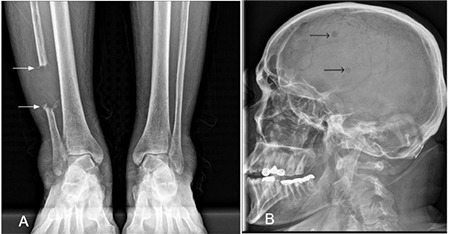

The Curious Tale of a Missing Bone Segment

Abstract Image